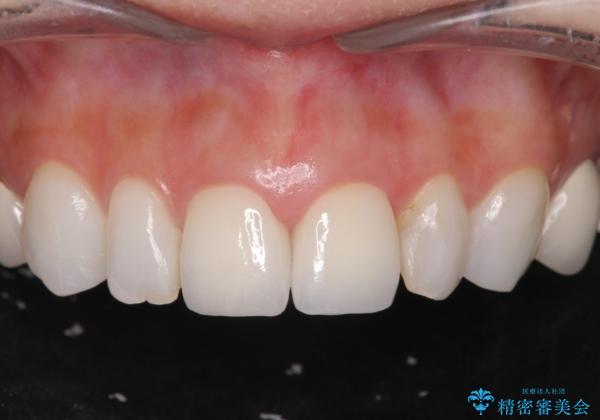

- 26.4万円(ジルコニアクラウン×2・仮歯×2)費用は治療当時の料金となります

歯の大きさの不揃いが改善されただけでなく、色調もよくなり審美性をしっかりと改善することができました。